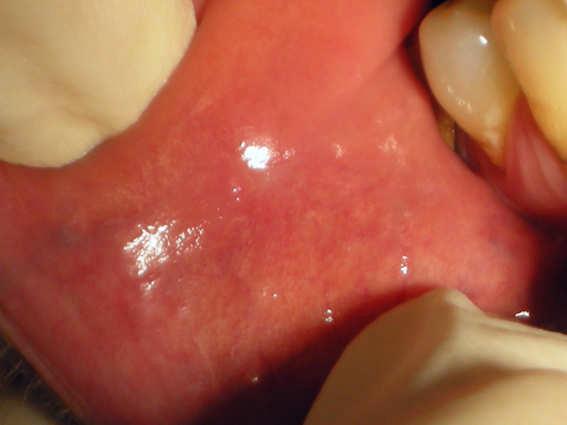

Morsicatio buccarum

Morsicatio buccarum (also known as "Chronic cheek biting," and "Chronic cheek chewing") is a cutaneous condition characterized by chronic irritation or injury to the buccal mucosa from repetitive chewing, biting or nibbling produces characteristic changes in the tissue.